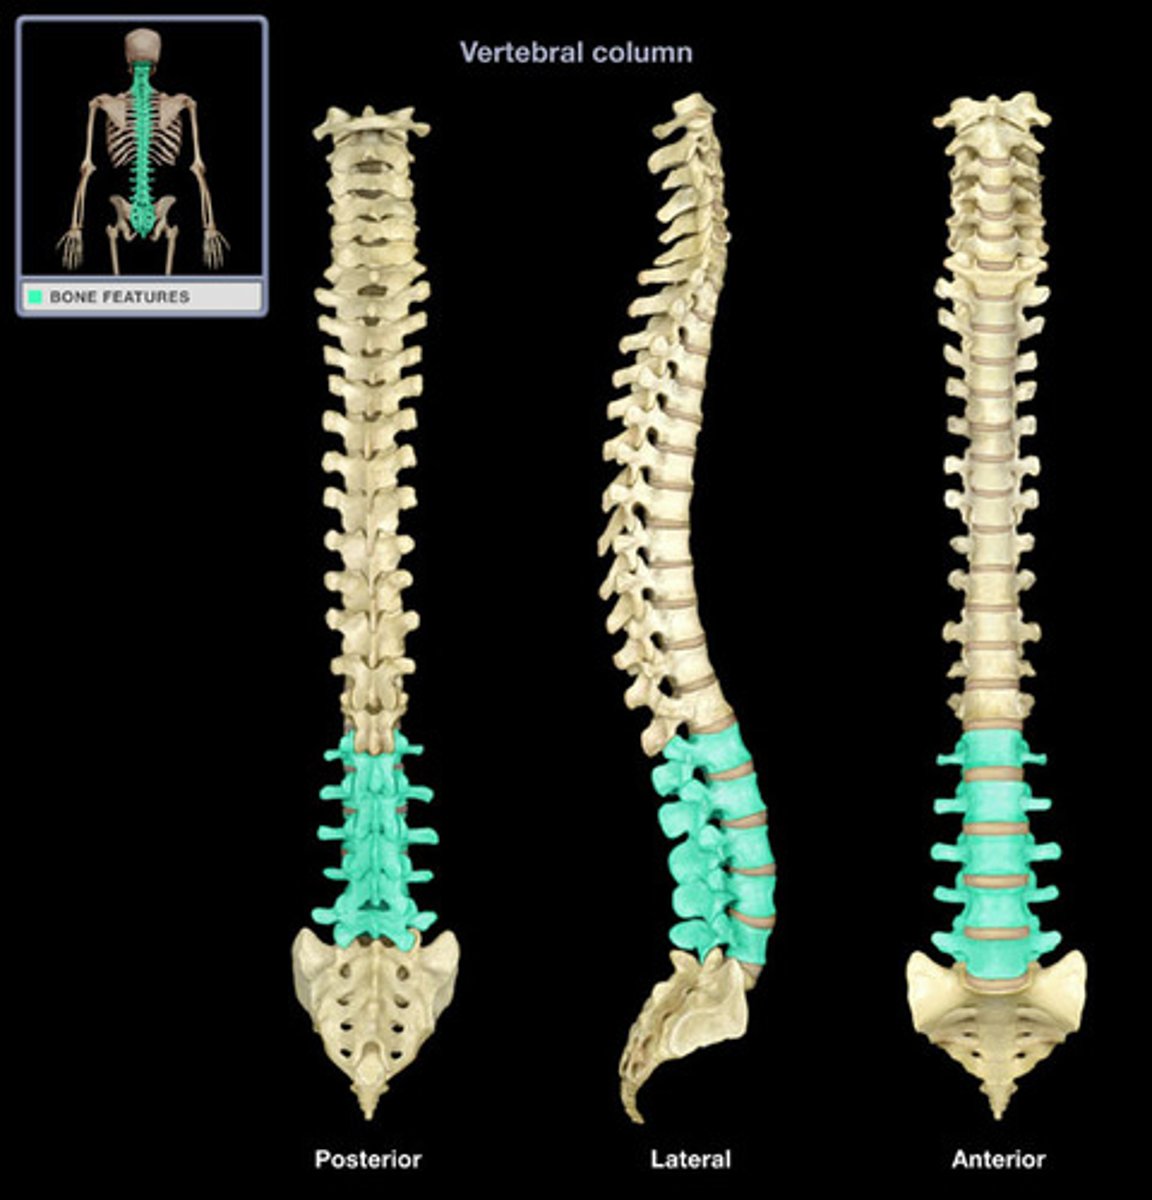

Spine (C/T/L), Sacrum & Coccyx

What are the sections of the vertebral column?

cervical, thoracic, lumbar, sacrum, coccyx

How many vertebrae make up the cervical spine?

7

How many vertebrae make up the thoracic spine?

12

How many vertebrae make up the lumbar spine?

5

How many vertebrae make up the sacral spine?

5 fused to form 1

How many vertebrae make up the coccyx spine?

3 to 5 fused to form 1